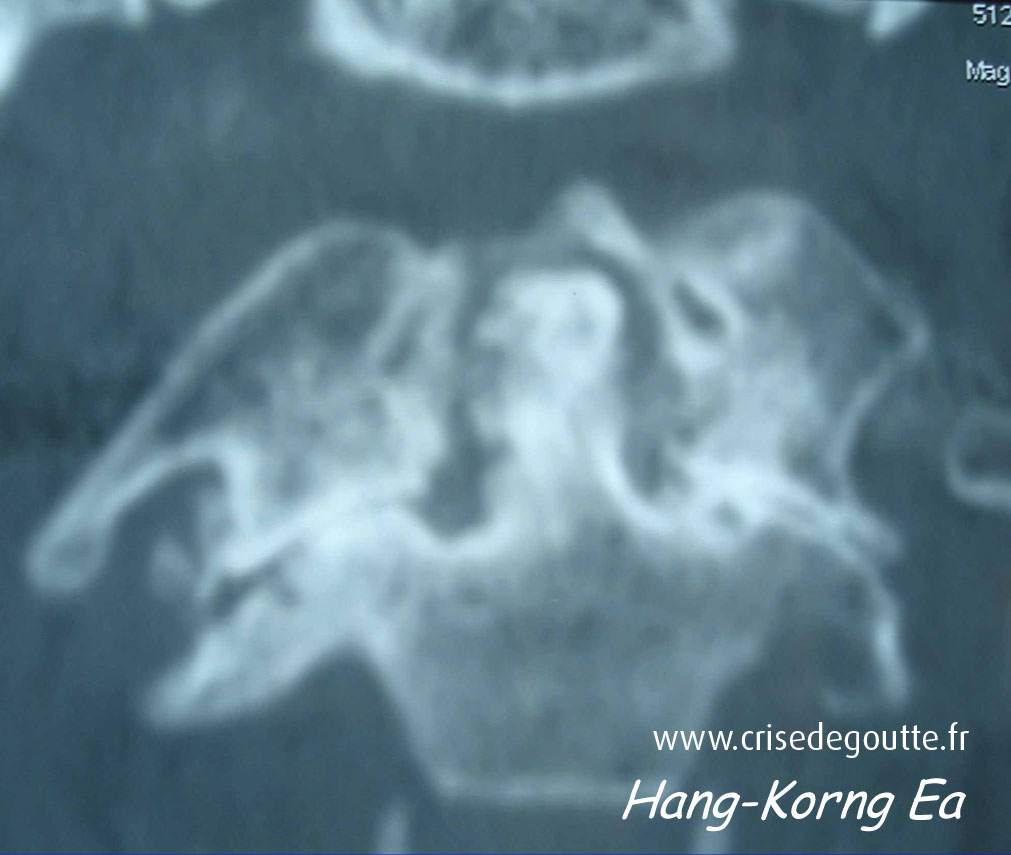

Imagerie

PPCD